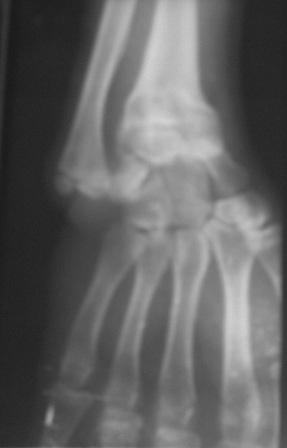

Доброго времени суток уважаемые коллеги! Обратился б-ной 16 лет.Травму получил 9-лет назад, перелом лучевой кости и надмышелковый перелом плеча. Имеется деформация л/з сустава типа лучевой косорукости, укорочение п/плечья, отсутствие локтевой девиации, cubitus vaus под углом 25 гр . Просит первоначально исправить деформацию л/з сустава и восстановить длину п/плечья. Наш план- остеотомия дистального метафиза лучевой кости, коррекция деформации и удлинение по методу Илизарова. Уважаемые коллеги, помогите советом! Можеть быть есть какие-то нюансы , или другие методы? Снимки прилагаются. С уважением Абдурашид.

С учетом возраста больного предлагаемая Вами тактика представляется оптимальной. Боковая ренгенограмма низкого качества, но кажется дистальный фрагментдостаточно короткий - надо постараться выполнить остеотомию точно на высоте деформации иначе трудно будет устранить угол.

Уважаемый Абдуращид, предложенный Вами план лечения адекватный и не вызывает сомнений.

Для полного представления о деформациях, желательно посмотреть рентгенограммы локтевого сустава.

И еще один момент, у пациента имеется укорочение всего сегмента, удлинение лучевой кости и коррекция угловой деформации не уровняет длину предплечья со здоровым. Это надо озвучивать и обсуждать с пациентом.

Уважаемый коллега, ваш план вполне логичен. Копенсация укорочения лучевой кости с коррекцией деформации. Устранения деформации только за счёт формирования клиновидного регенерата думаю будет недостаточно для компенсации укорочения. В связи с этим целесообразно монтировать аппарат с учётом формирования трапецевидного регенерата.

U bolnogo po vidimomu byl growth arrest of the distal radius.

Ya by ne nakladyval nikakih external, namnogo proche ukorotit distal ulna , fixation by plate , and corrective distal radius osteotomy(moghno zafixirovat KW ).6-8 weeks cast i vse dela.Ya za Ilizarova , no na kisti esli moghno bez nego vsegda luchshe.Predloghennaya techika ochen legk perenositsya (delal mnogo raz sam)